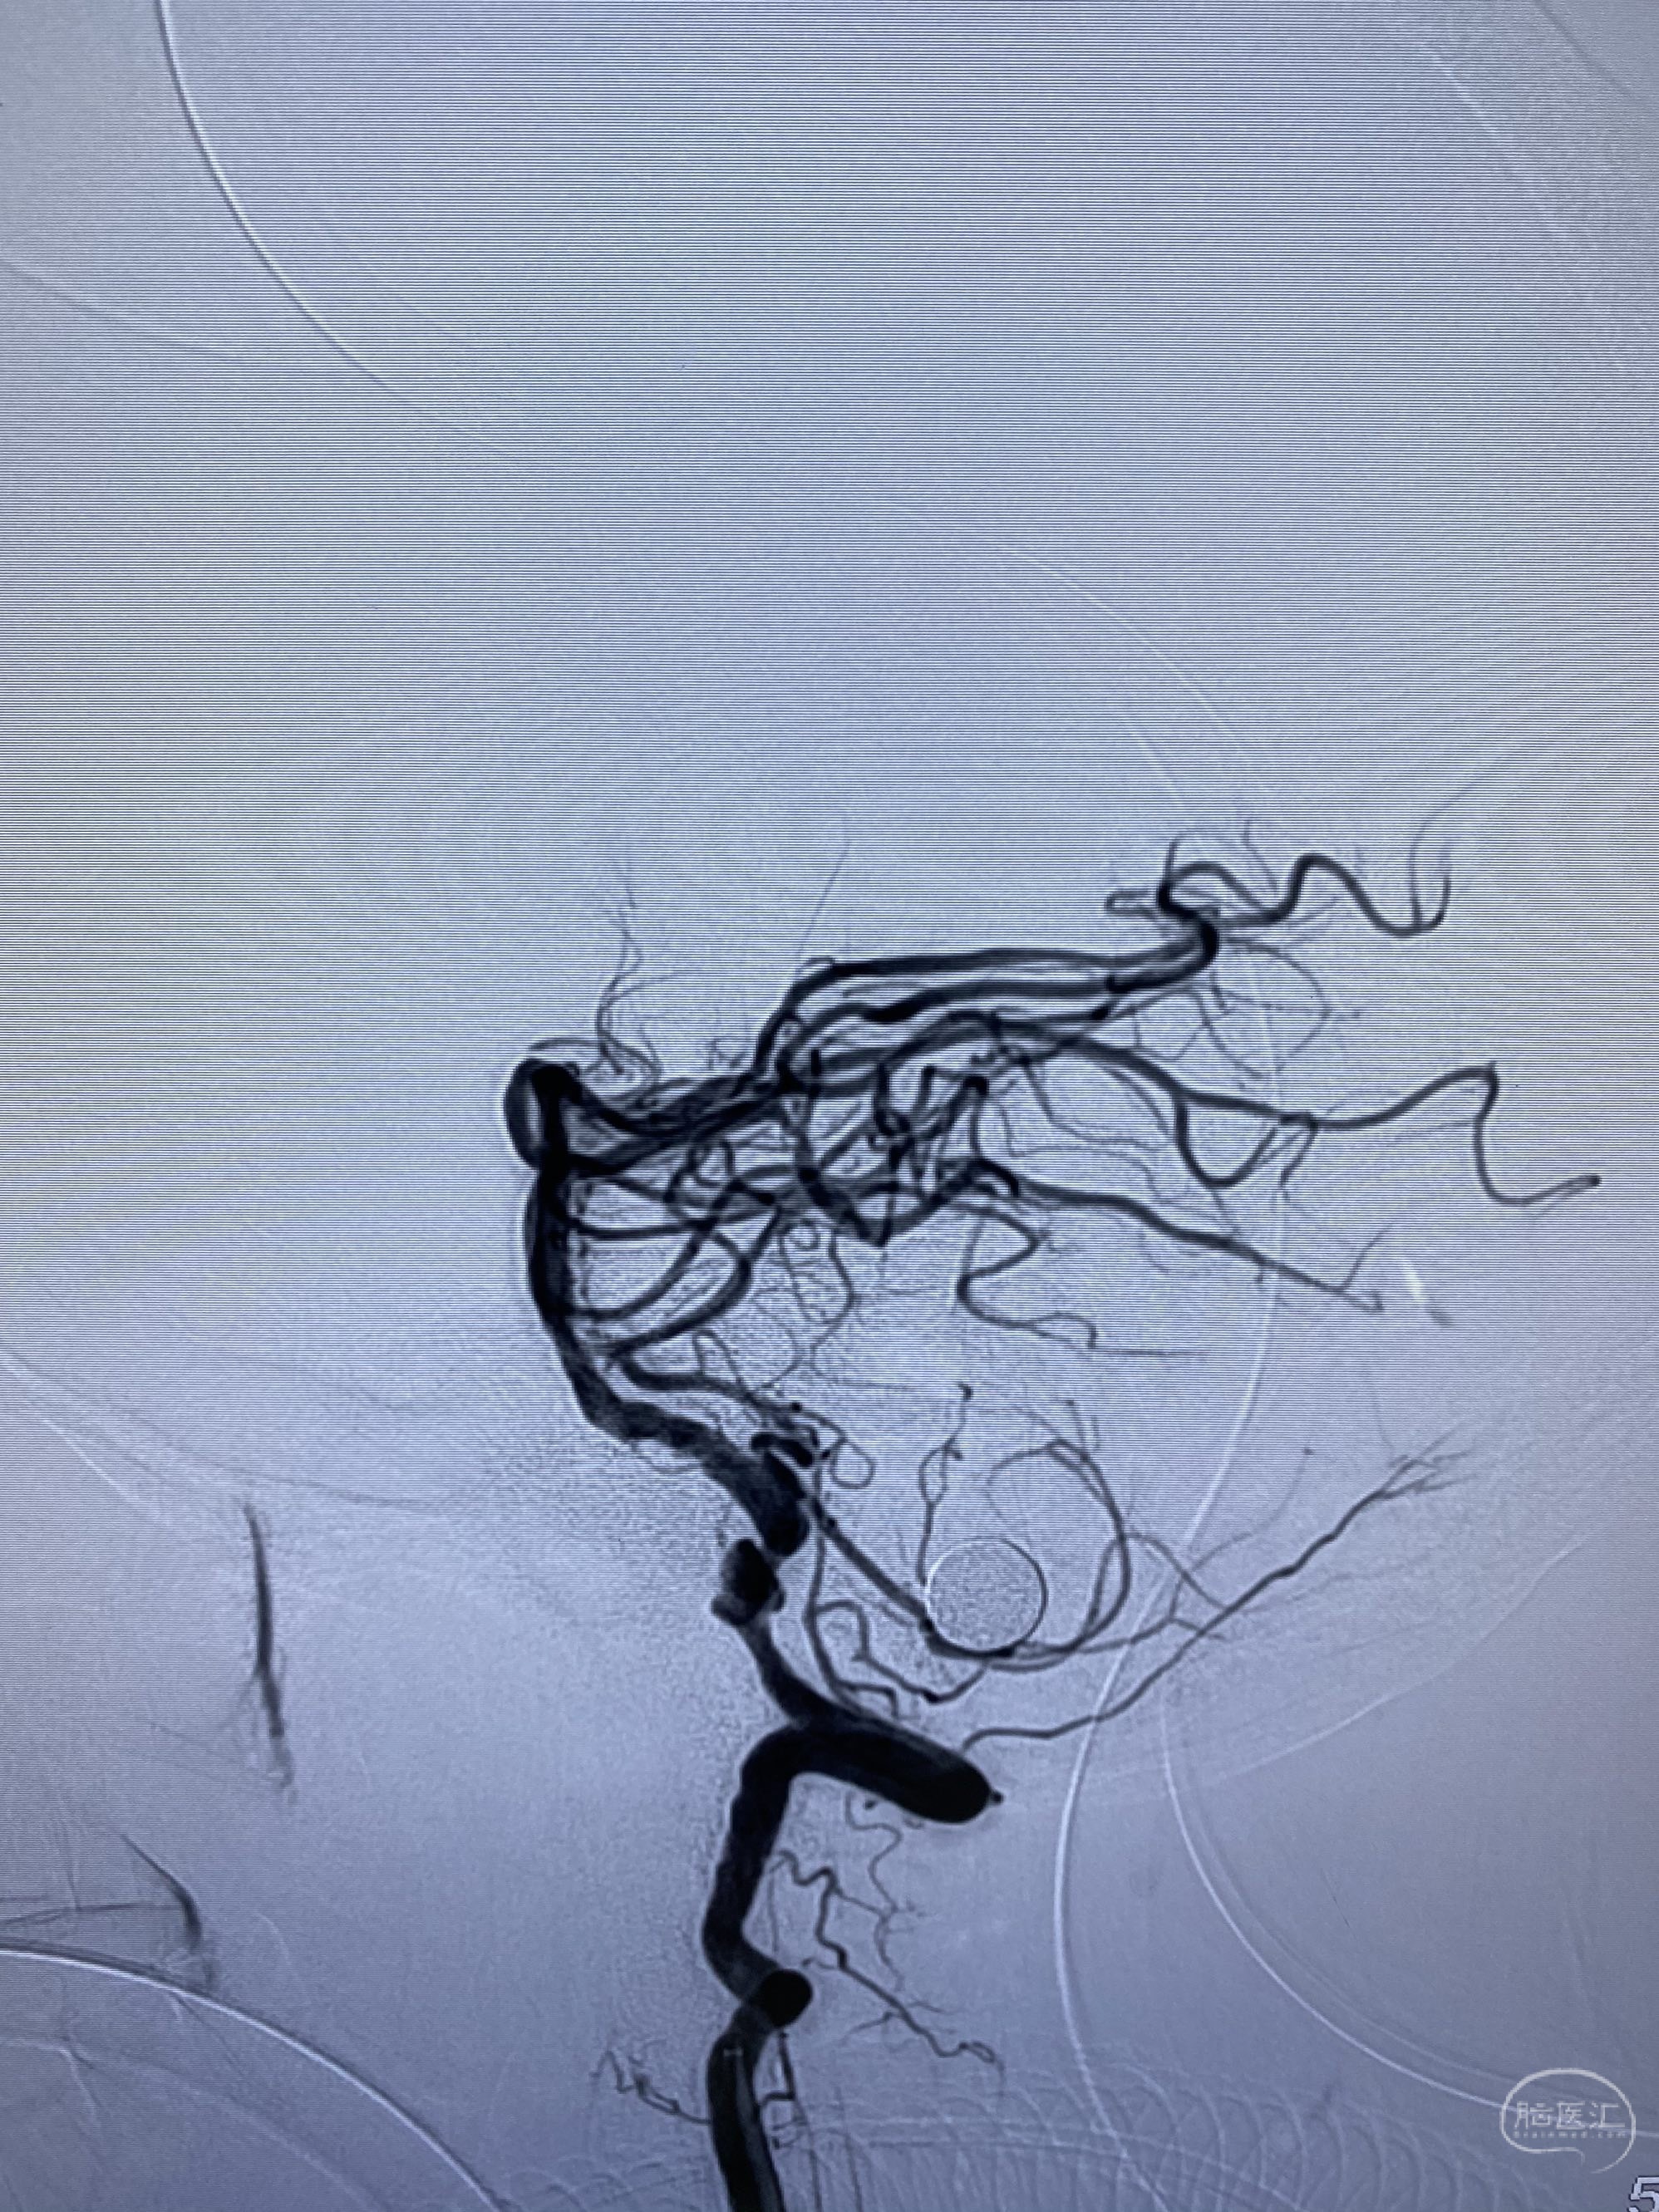

椎动脉颅内段多发夹层动脉瘤伴载瘤动脉狭窄pipeline flex植入

今日手术,TJG,M62Y,一期左侧颈动脉狭窄支架植入,二期椎动脉V4段多发夹层动脉瘤伴狭窄,常规支架辅助栓塞方法复杂又危险,血流导向装置植入快捷又安全。南阳市中心医院神经内科脑血管病介入团队pipeline flexFD植入两人导师资格。